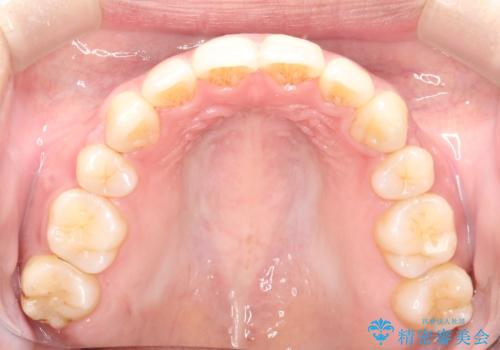

- クリアブラケット

- 2年2ヶ月

上顎の前から両側の前から4番目の歯と、下あごの前歯を1本抜歯して、口元をすっきりさせる計画としました。